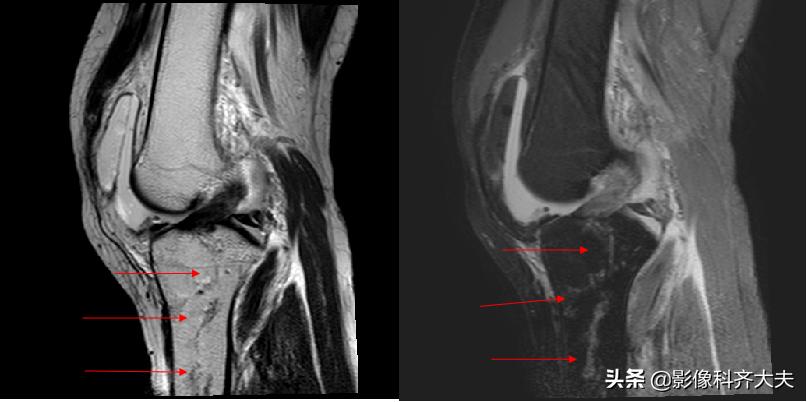

骨挫伤(bone bruise):外力作用引起的骨小梁断裂和骨髓水肿、出血,T1WI低信号,T2WI高信号,压脂序列显示清晰。平片和CT 上常无异常发现。

例:右胫骨骨挫伤

右胫骨骨挫伤-MRI清晰显示病灶位置

MRI检查

椎体楔状变形

急性期椎体压缩骨折,由于水肿T1WI呈低信号,T2WI信号增高

骨折的椎体压迫脊髓、脊髓水肿、脊髓出血、脊髓断裂及脊髓软化均可显示清楚

椎体压缩骨折可合并前后纵、棘间韧带断裂,可见其连续性中断及信号异常

椎间盘碎裂,表现为形态不规则及T2WI 异常高信号,并可突出压迫脊髓